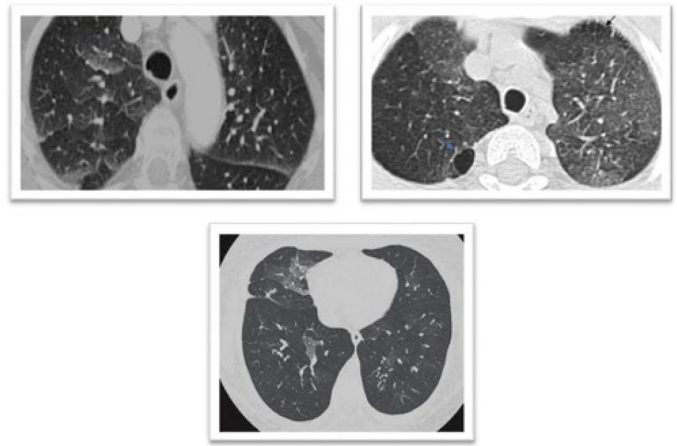

本研究针对幼年特发性关节炎(JIA)患儿肺部并发症早期诊断难题,通过HRCT影像学与炎症标志物(ESR、CRP、Ferritin)的关联性分析,发现36.7%患儿存在间质性肺病(ILD)影像学特征,其中54.5%为无症状患者。结果表明HRCT可作为JIA患儿亚临床肺部病变的敏感检测手段,为临床早期干预提供重要依据。